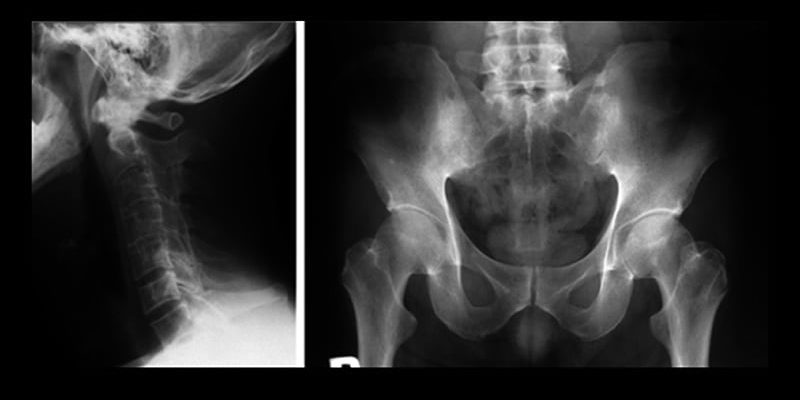

OBERSTEN ZEILE:Die nichtradiologische axiale Spondyloarthritis (nr-axSpA) entwickelte sich bei etwa 16 % der Erwachsenen mit neu aufgetretener Erkrankung innerhalb eines Zeitraums von 5 Jahren zu einer radiologischen Erkrankung (r-axSpA). Das Fortschreiten war signifikant mit dem männlichen ...